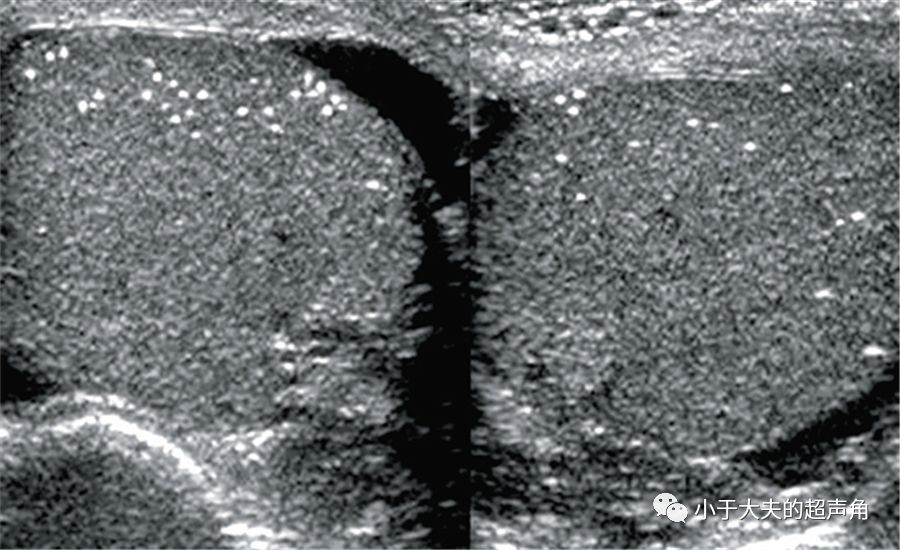

可见睾丸大小形态正常,回声均匀,内可见数个粗大强回声钙化灶(长箭)

患男14岁,双侧睾丸弥漫性钙化.